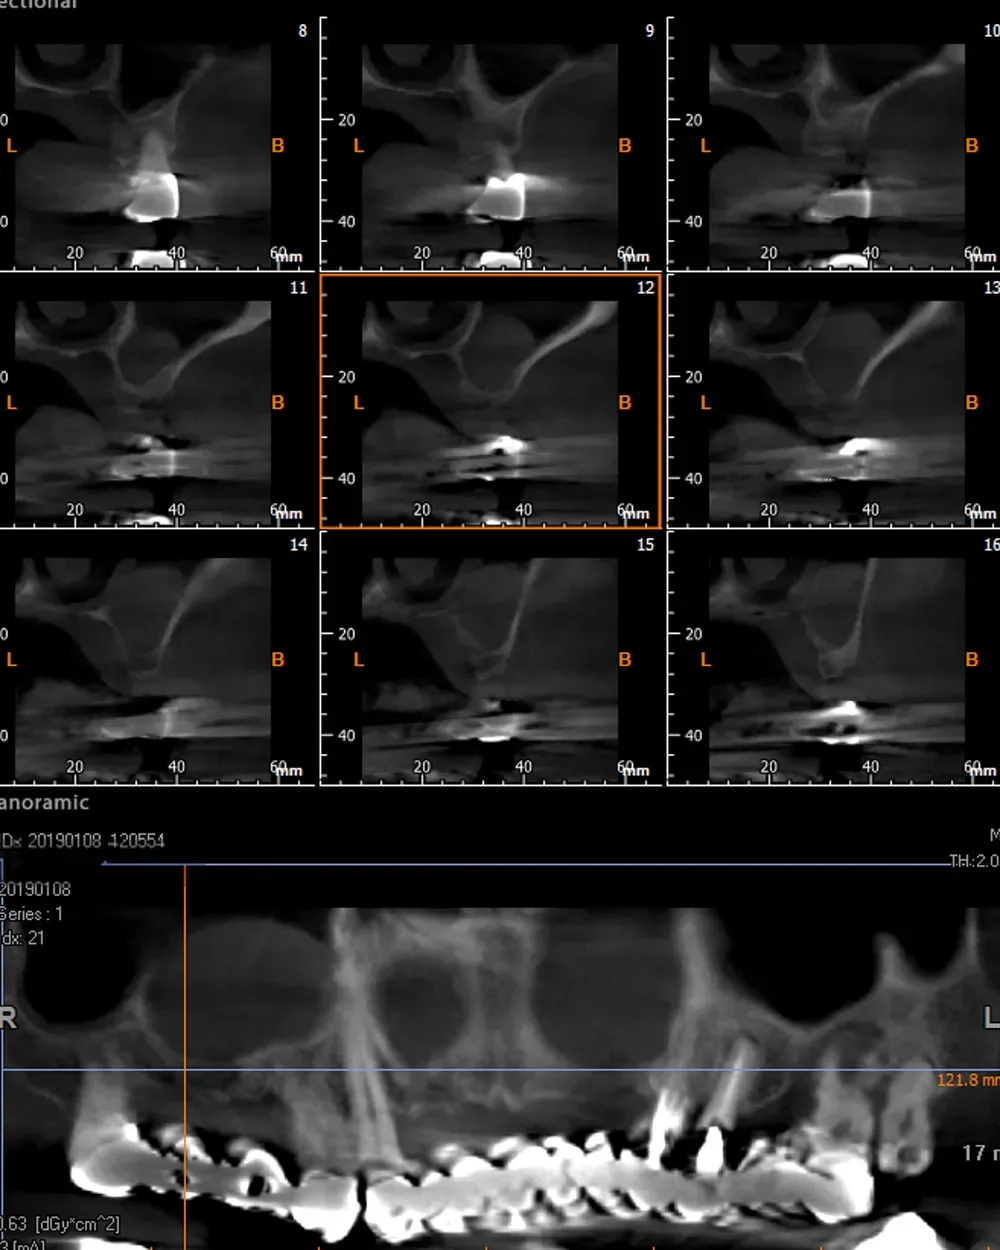

Il controllo a distanza di anni

Al controllo radiografico, sette anni più tardi, gli impianti sono in ottima salute e perfettamente integrati (vedi immagini seguenti).

Francesco viene regolarmente ai controlli, in particolare per le sedute di igiene professionale.